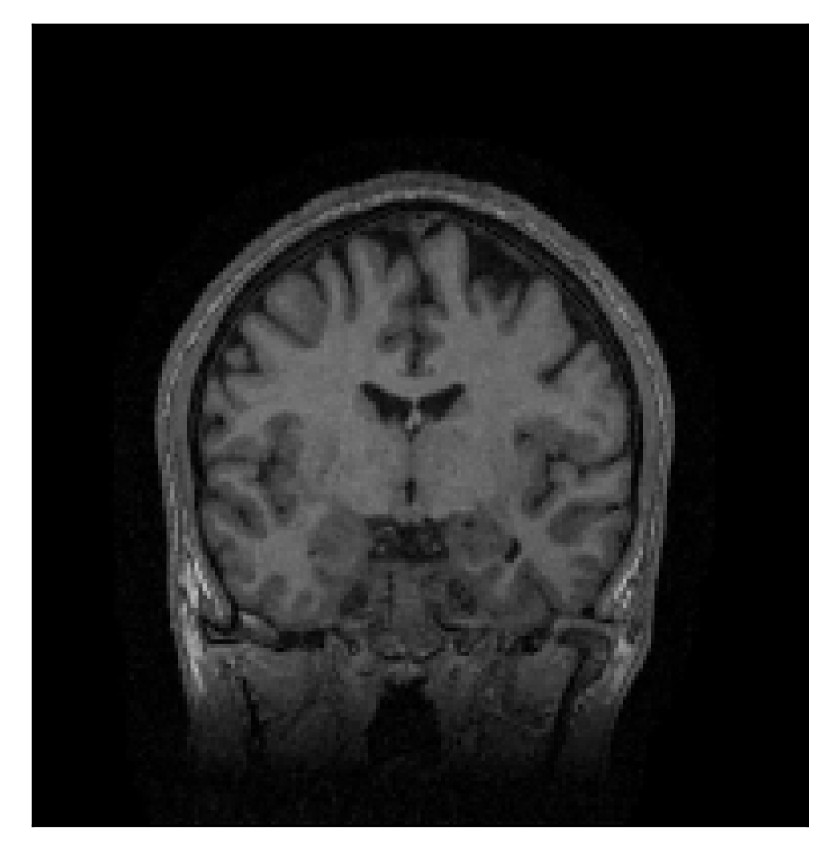

| Section 3.1, Figure 4 | Sagittal | 25.78 | 27.76 | 0.7263 | 0.7816 |

| Coronal | 28.19 | 29.73 | 0.7847 | 0.8244 | |

| Axial | 27.79 | 29.70 | 0.8104 | 0.8362 | |

The motion-corrected full-volume scans were analyzed by a neuroradiologist with 16 years of experience. These were generally deemed of good radiological quality. The motion-related artifacts have been completely removed, and the results are quite close to the ground truth. In Table 3, we organized a more detailed qualitative analysis of the 3D results, geared toward a radiological assessment of the corrected scans.

| Experiment | Contrast | Motion resolution | Blurring | Artifacts | Additional comments |

| Section 3.1, Figure 4 | T2-FLAIR | Completely corrected | Some blurring | No additional artifacts | Good grey white matter differentiation |

4.1 Experiment 1: robustness test

We gather the results for the robustness test described in Section 3.1 (volunteer 1) in Figures 2, 4, and 6 for motion corruption mechanisms associated to one, two, and five changes of position, respectively. Furthermore, we juxtapose the corrected images with varying degrees of corruption in Figure 8. We observe that the proposed method consistently ameliorates the corrupted scan. The quality indexes based on PSNR and SSIM show only a modest decrease in correction quality as a function of motion complexity (Figure 8).

Our experimentation based on volunteer data aimed at assessing the robustness of the correction quality with respect to motion artifacts of increasing complexity. In this study, we equated this complexity to the number of volunteer changes of pose during the acquisition phase. Clearly, this does not fully describe the complexity of motion encountered in practice in the clinic, but it only constitutes a preliminary step in that direction. Nevertheless, the results described in Section 4.1 support the indication that the retrospective motion correction of T2-FLAIR weighted images based on a T1 reference contrast is quite robust in terms of reconstruction quality, with only minor degradations in terms of contrast and resolution.